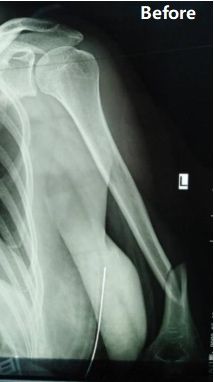

Case Sharing | Fratura do úmero diafisário médio a distal do terceiro

Resumo do Caso: Paciente do sexo feminino, 48 anos, foi diagnosticada como fratura do terço médio-distal da diáfise umeral esquerda (classificação AO: tipo B1).

A equipe cirúrgica optou pela Osteossíntese de Placa Minimamente Invasiva (MIPO) através da abordagem anterior usando um Sistema Ortho-Bridge (OBS). A cirurgia foi concluída com sucesso em 90 minutos, com perda sanguínea estimada de aproximadamente 150 ml e comprimento de incisão de cerca de 8 cm.